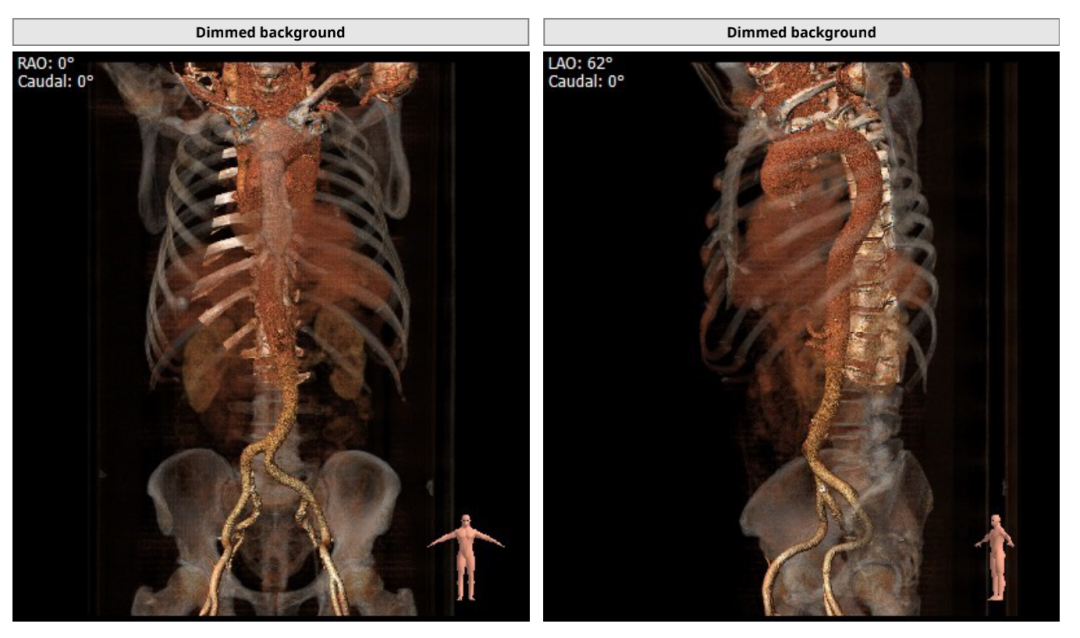

CT评估

主动脉根部解剖结构

瓣环直径:26.9mm,左室流出道直径:27.7mm

主动脉窦:36.2*37.5*36.8mm,STJ:31.4mm

左冠高度:13.0mm,右冠高度:19.4mm

升主动脉直径:38.3mm,心脏夹角:48度

钙化积分及分布

入路情况